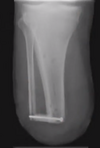

28

# Amputações - Na amputação transtibial, qual técnica operatória diminui a instabilidade tibiofibular proximal e proporciona um coto mais estável?

- **Sinostose tibiofibular distal (técnica de Ertl)**